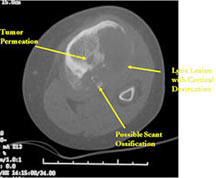

- Permeative lesion with indistinct border that is poorly marginated

- Osteolytic and expansile on X-ray with very little osteoid production

- Osteoid usually not discernible on X-ray but scant and faint lace-like osteoid may be detectable on a CT scan

- No surrounding sclerosis

- May have Codman’s triangle and malignant appearing periosteal reaction in most cases

- Cortical destruction and soft tissue extension are common

MRI/CT:

- MRI and CT are also useful for demonstrating the local extent of the tumor and any soft tissue mass

- CT also useful for demonstrating scant osteoid production